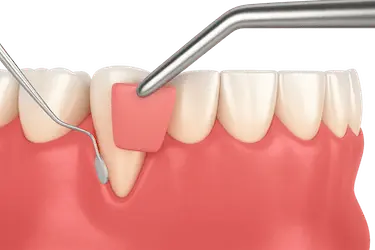

Cirugía colgajo dental

Es un tipo de cirugía periodontal. Consiste en la separación de la encía del diente para llegar de forma directa a la bolsa periodontal.

Posteriormente, nuestros especialistas vuelven a unir la encía y el diente, lo que da lugar a una mayor adhesión entre ambos en el futuro. Con ello se previene la pérdida de la pieza.